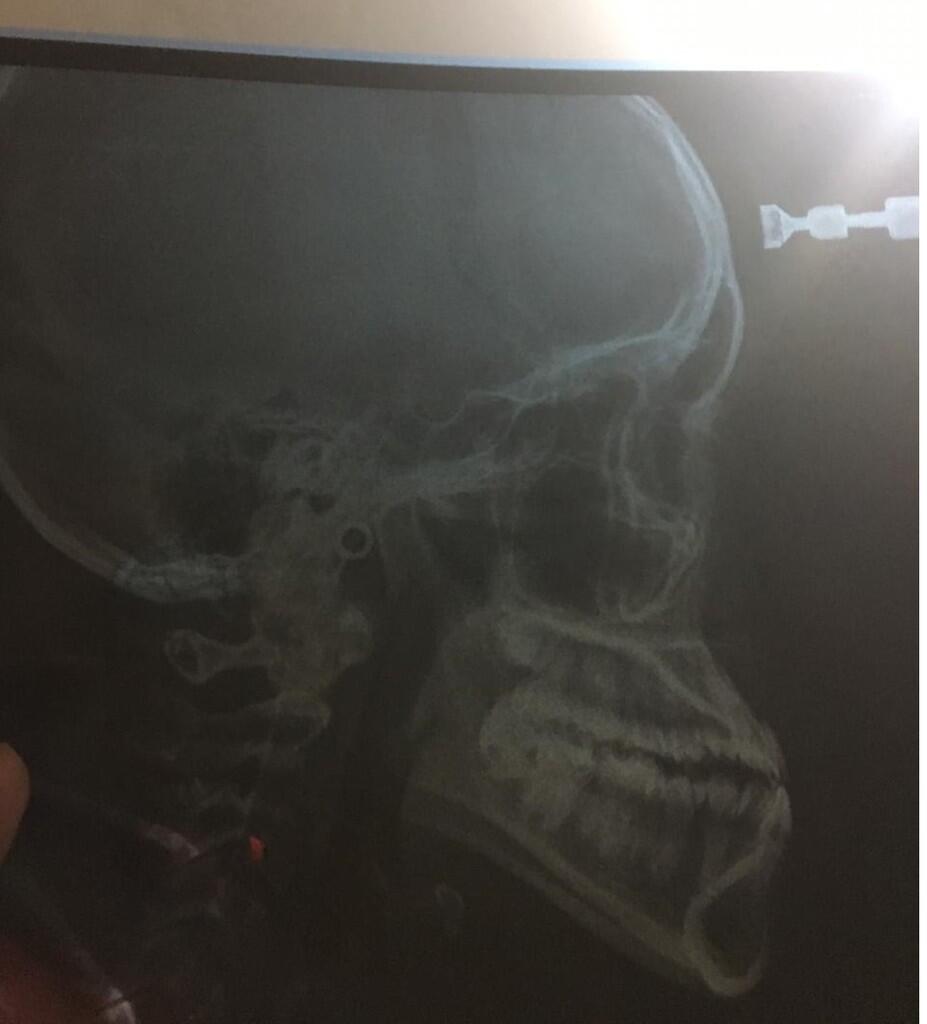

Halo gan, ane umur 20 dan sejak lama punya panggilan "si Cameuh" karena rahang bawah ane maju (foto diatas bukti Xray ane). Awalnya biasa aja tapi lama2 ane enek juga gan, akhirnya minggu lalu ane pergi ke klinik gigi terkemuka dengan niat awal mau pasang braces/behel. Sesampainya disana, oleh dokter gigi nya ane diperiksa dan menurut beliau gigi ane ini masuk ke Class 3, yang udah parah banget dan gak akan bisa dibetulkan dengan behel. Akhirnya kasus ane ini ditolak dan ane disarankan untuk ke spesialis orthodonti untuk bedah skeletal, baru setelah itu bisa dilanjut dengan behel.